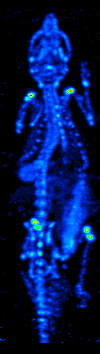

Метод проекции максимальной интенсивности крайне прост и позволяет при небольших вычислительных затратах показать положение в трёхмерном пространстве наиболее ярких участков трёхмерного объекта — таких, как опухоли. С протяжёнными объектами примерно постоянной интенсивности (такими, как рёбра на анимации справа) метод проекции максимальной интенсивности справляется хуже.